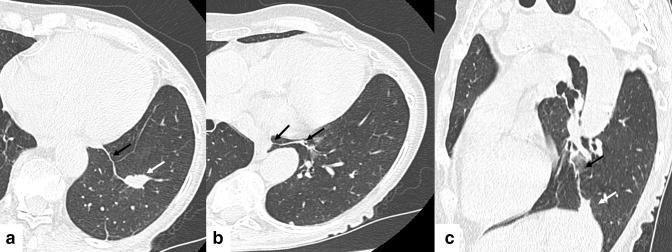

The inferior pulmonary ligament and related connective tissue septa are a recognizable site of granulomatous lymphadenitis on CT of the chest and may mimic a lung parenchymal lesion. The anatomy of the inferior pulmonary ligament, CT appearances and potential etiologies of this entity are reviewed and illustrated.

肺下韧带及相关结缔组织间隔是胸部CT上肉芽肿性淋巴结炎的一个可识别部位,可能酷似肺实质病变。本文回顾并举例说明了肺下韧带的解剖结构、CT表现及该病变的潜在病因。